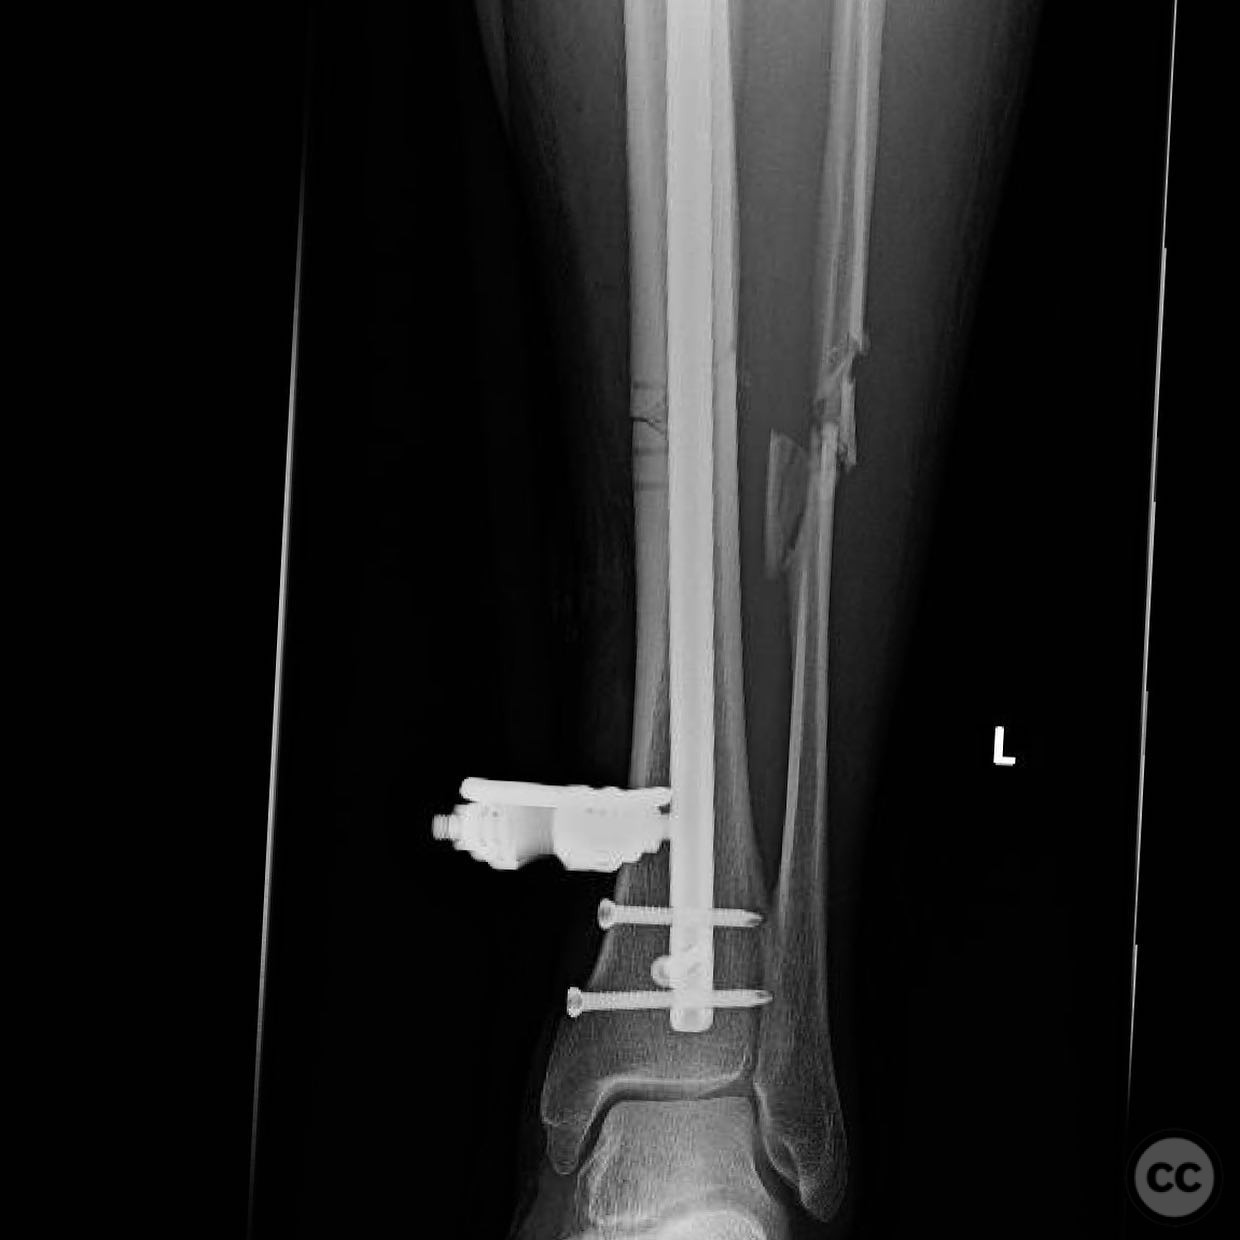

Anatomical surgical approach:  For the tibia, a longitudinal incision was made to access the proximal tibial start site for intramedullary nailing. Percutaneous clamps were utilized for reduction, supplemented by blocking screws as needed. For the distal femur, an external fixator was applied initially, followed by an in situ lateral approach for plating after reduction was achieved.

The tibial nailing required precise identification of the start site under fluoroscopic guidance, with percutaneous clamps aiding in reduction. Blocking screws were considered but not necessary due to successful reduction with clamps alone. The distal femur presented challenges in achieving coronal and sagittal alignment, necessitating reliance on the external fixator for reduction before proceeding with plating.

Postoperative protocol:   Postoperative rehabilitation included early mobilization with weight-bearing as tolerated on the tibia, while the femur required protection until definitive fixation was achieved. Progressive weight-bearing was introduced following femoral plating.

Orthopaedic implants used:   Intramedullary nail for tibia, external fixator for initial femoral stabilization, and locking plate for definitive femoral fixation.